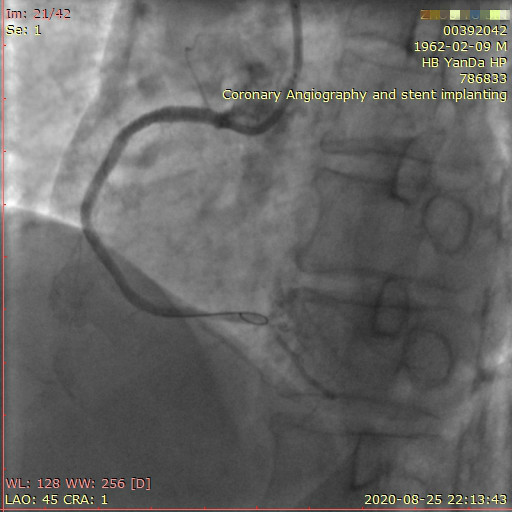

近日,河北燕达医院心血管内三科成功完成一例非常特殊的手术——冠心病三支病变微创介入完全血运重建术。患者李先生冠心病病变极其严重,全部三支主干动脉均重度狭窄,各处求诊均被告知无法微创介入手术,只能开胸搭桥。拒绝开胸的李先生慕燕达医院心血管内三科北京安贞医院专家团